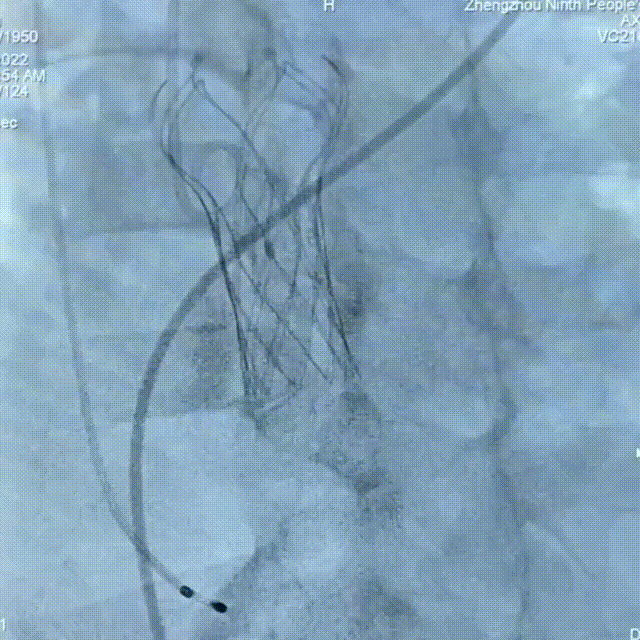

术中操作

18mm球囊预扩

TAV24瓣膜精准定位

缓慢释放至1/3

瓣膜脱钩释放

22mm球囊后扩

术后造影